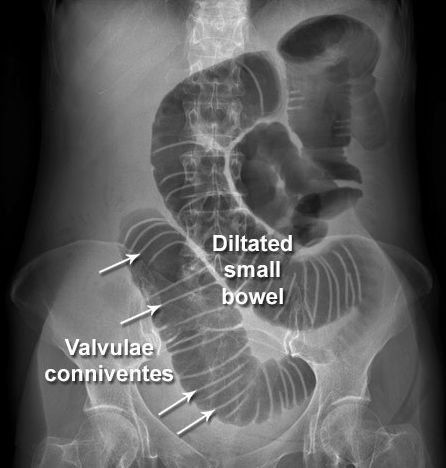

21

Q

24-year-old patient with suspected appendicitis. What does the image show?

Caecal volvulus

Normal appearances

Pneumoperitoneum

Small bowel obstruction

Toxic megacolon

A

Dilated loops of bowel with valvulae conniventes – lines crossing the full width of the bowel – indicates small bowel obstruction.

How well did you know this?

Describe what is seen in this AXR [3]

**Small bowel obstruction - features** **Centrally located** multiple dilated loops of gas filled bowel (arrowheads) **Valvulae conniventes** (arrow) are visible - confirming this is small bowel